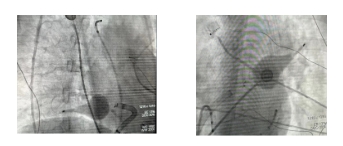

消融前使用三维电解剖标测对肺静脉走形以及原始肺静脉电位。随后将三维标测导管更换为X3球囊型激光消融导管进行肺静脉隔离。在内窥镜的指引下很轻松地完成了四根肺静脉的隔离,用时不到30分钟。

通过内窥镜观察消融无漏点后再次三维电解剖标测确认肺静脉电位全部隔离,手术圆满成功。术后患者状态良好,无不良反应。